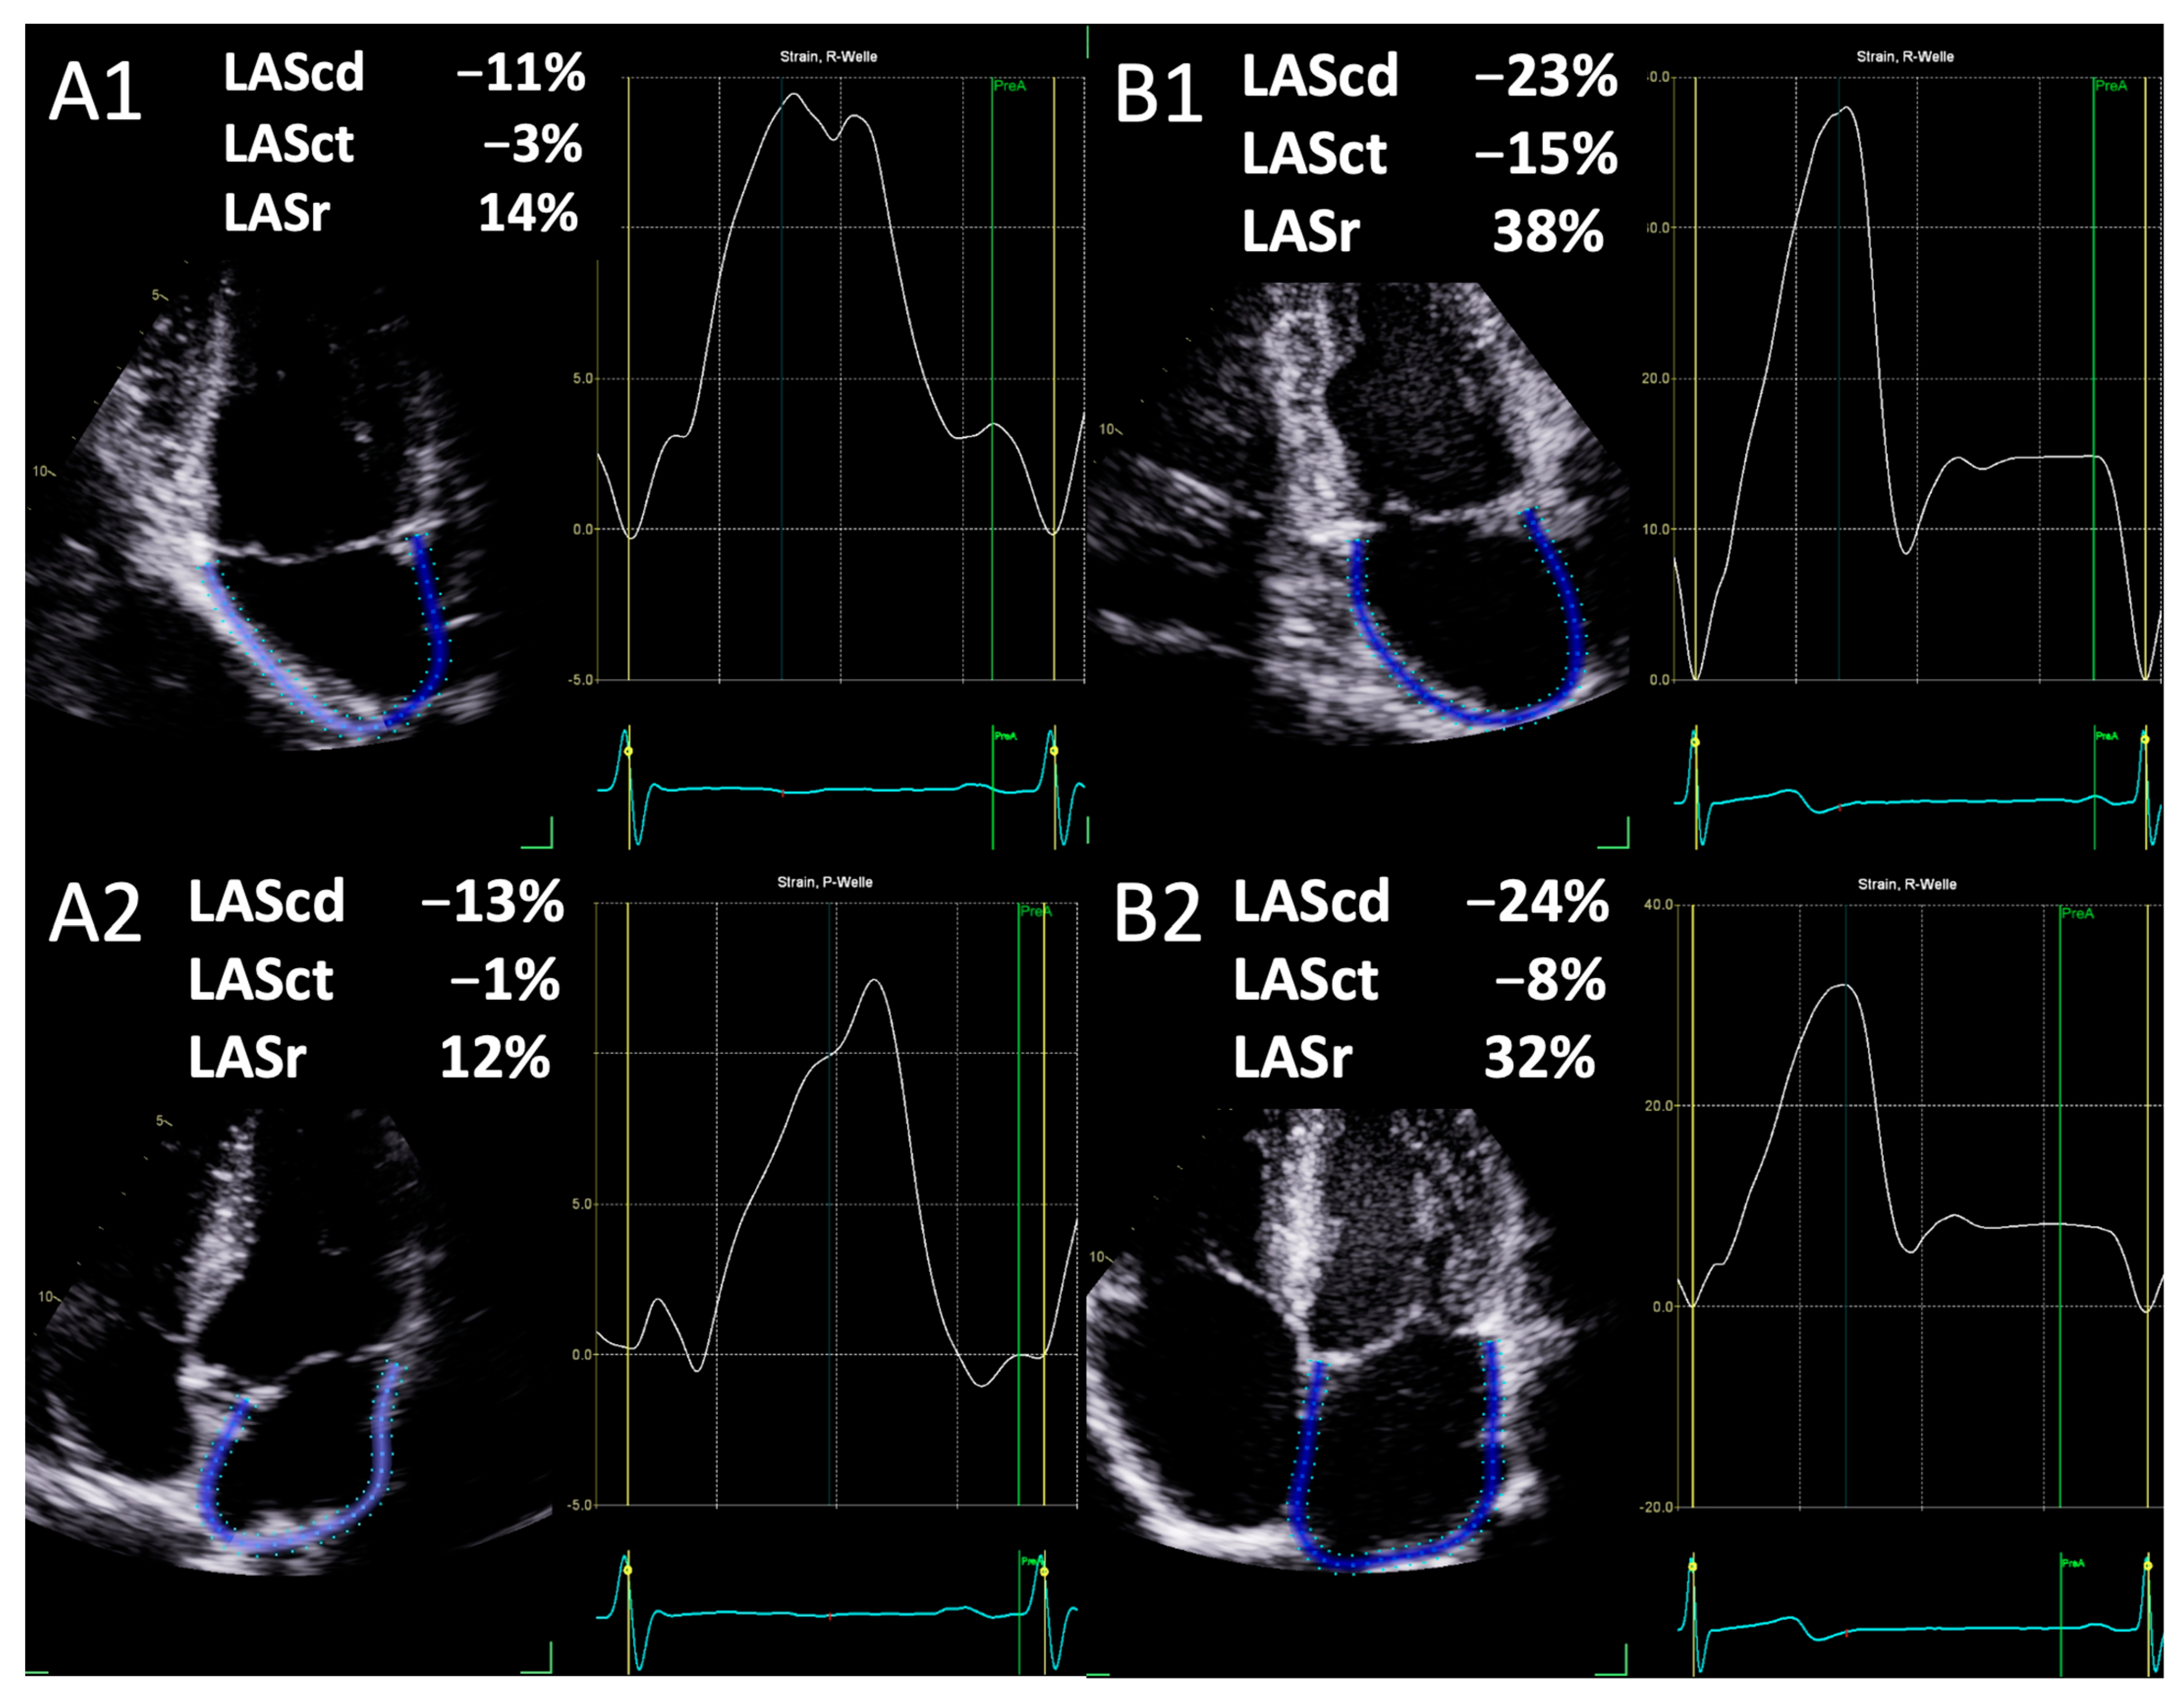

| 4 Chamber View | |||

| Conduction Strain (%) | −13.9 ± 6.5 | −26.9 ±6.9 | <0.001 |

| Contraction Strain (%) | −4.0 ± 3.3 | −9.0 ± 4.1 | <0.001 |

| Reservoir Strain (%) | 17.9 ± 7.5 | 34.4 ± 13.4 | <0.001 |

| 2 Chamber View | |||

| Conduction Strain (%) | −14.0 ± 7.8 | −27.7 ± 9.0 | <0.001 |

| Contraction Strain (%) | −5.4 ± 4.9 | −12.2 ± 9.9 | <0.001 |

| Reservoir Strain (%) | 19.6 ± 10.4 | 41.6 ± 9.7 | <0.001 |

| Biplane | |||

| Conduction Strain (%) | −14.0 ± 5.9 | −27.4 ± 7.1 | <0.001 |

| Contraction Strain (%) | −4.6 ± 3.5 | −11.3 ± 4.1 | <0.001 |

| Reservoir Strain (%) | 18.7 ± 7.6 | 38.7 ± 8.0 | <0.001 |